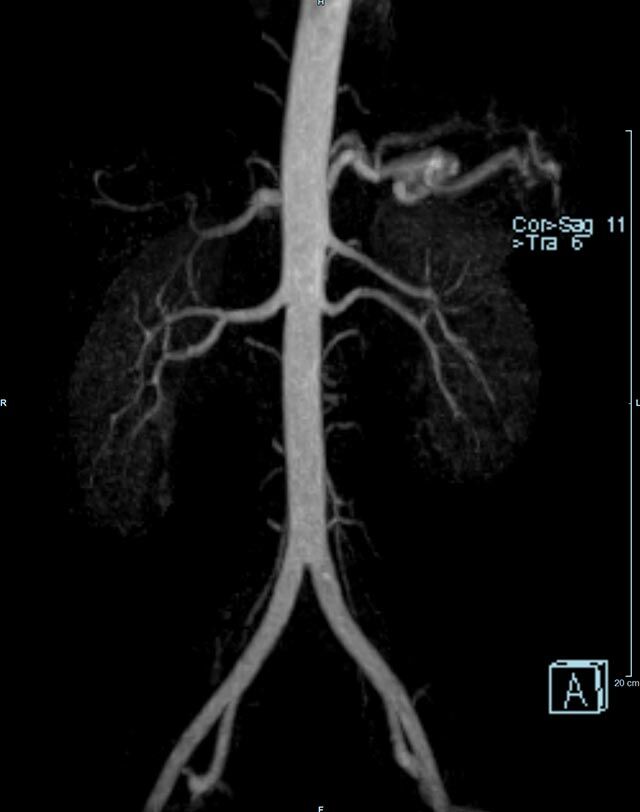

• Bauchgefäße

• Erfassung und Verlaufskontrolle bei arteriellen Aneurysmen (Aussackungen der Arterien), vor allem der Bauchaorta

• Darstellung von Gefäßengen an Nierenarterien, Baucharterien und Becken-/Beinarterien

MR-Angiografie (MRA)

• MR-Angiographie mit Kontrastmittel

• Erfassung arterieller und venöser Gefäße/Bypässe aller Körperregionen mit 3D-Rekonstruktion